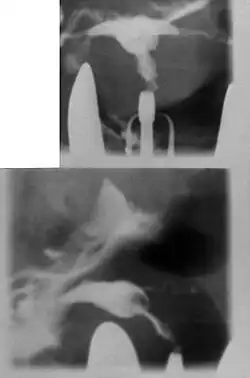

Hysterosalpingography of a T-shaped uterus.

A T-shaped uterus with circular constriction noted around the proximal portion of the marker. The lower uterus appears tapered and narrow.

Women are often diagnosed with this condition after several failed pregnancies, proceeded by exploratory diagnostic procedures, such as magnetic resonance, sonography, and particularly hysterosalpingography.[6][7][8] In such studies, a widening of the interstitial and isthmus of uterine tube is observed, as well as constrictions or narrowing of the uterus as a whole, especially the lower and lateral portions, hence the "t" denomination. The uterus might be simultaneously reduced in volume, and other abnormalities might be concomitantly present.[9]